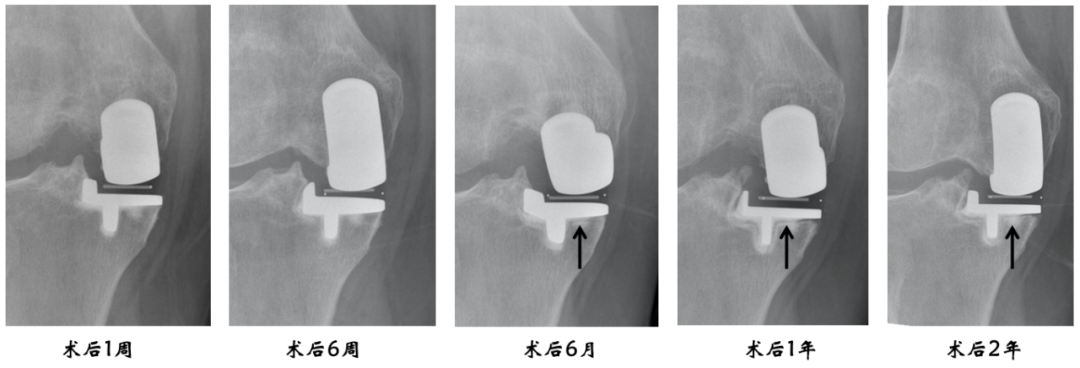

透亮线形成过程

透亮线的意义

生理性透亮线的定义:

宽度≤2mm、边界清晰锐利、非进行性增宽,常伴平行致密硬化线。在术后头两年形成,随后保持稳定。不提示假体松动、感染或失败。